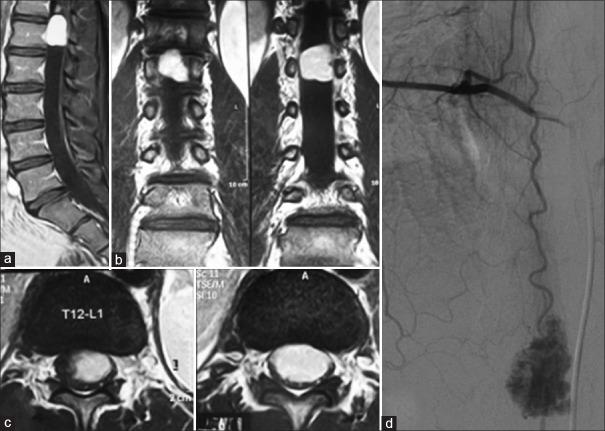

Hemangiomas have rarely been found in the spinal cord. A few cases of spinal capillary hemangioma have been reported since 1987. The authors reported the two cases of capillary hemangioma including the tumor at conus medullaris and the another mimicked von Hippel-Lindau disease. A 15-year-old man was presented with coccydynia and left leg pain. A magnetic resonance imaging (MRI) revealed an intradural extramedullary enhancing mass at conus medullaris. Another case, a 31-year-old man was presented with a history of familial history of brain tumor, retinal hemangioma both eyes, multiple pancreatic cyst and syringobulbia with syringohydromyelia. On MRI, a well-circumscribed intramedullary nodule was detected at C5-6 level and multiple subpial nodule along cervicothoracic spinal cord. All patients underwent surgery, and the histological diagnosis confirmed capillary hemangioma. Although rare and indistinguishable from other tumors, capillary hemangioma should be in the differential diagnosis of the spinal cord tumor.

脊髓海绵状血管瘤罕见。自1987年以来,已有少数脊髓毛细血管瘤病例报告。作者报告了两例毛细血管瘤病例,其中一例肿瘤位于脊髓圆锥,另一例类似von Hippel-Lindau病。一名15岁男性表现为尾骨痛和左腿疼痛。磁共振成像(MRI)显示脊髓圆锥硬膜内髓外强化肿块。另一例,一名31岁男性有脑肿瘤家族史、双眼视网膜血管瘤、多个胰腺囊肿以及伴有脊髓空洞症的延髓空洞症病史。MRI显示C5-6水平有一个边界清晰的髓内结节以及颈胸段脊髓多处软膜下结节。所有患者均接受了手术,组织学诊断证实为毛细血管瘤。尽管罕见且与其他肿瘤难以区分,但毛细血管瘤应列入脊髓肿瘤的鉴别诊断。